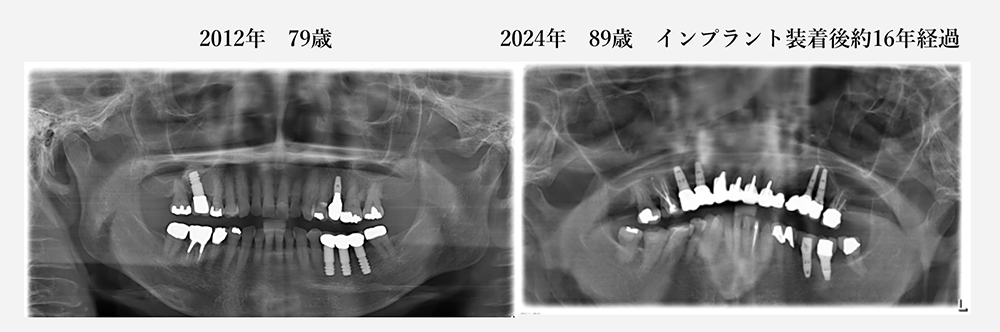

当院で20年以上メインテナンスをしていて、歯を抜くこともなく、

80歳を過ぎてもご自分の歯で美味しく食事ができています。

(デジタルレントゲン導入(2011年)後のレントゲン写真のみとなります)

現在89歳の女性